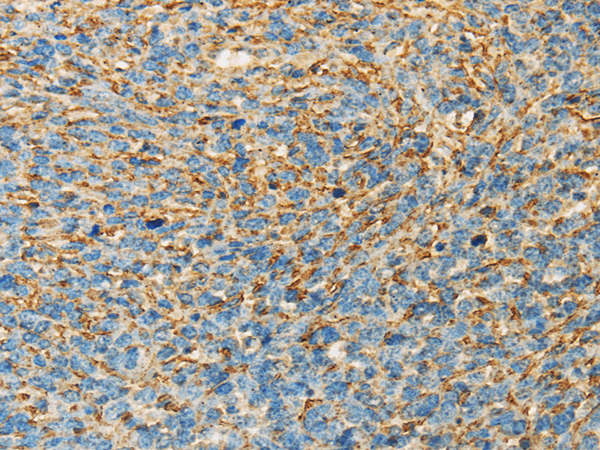

IHC positive control: |

Human ovarian cancer and human cervical cancer |

IHC Recommend dilution: |

25-100 |